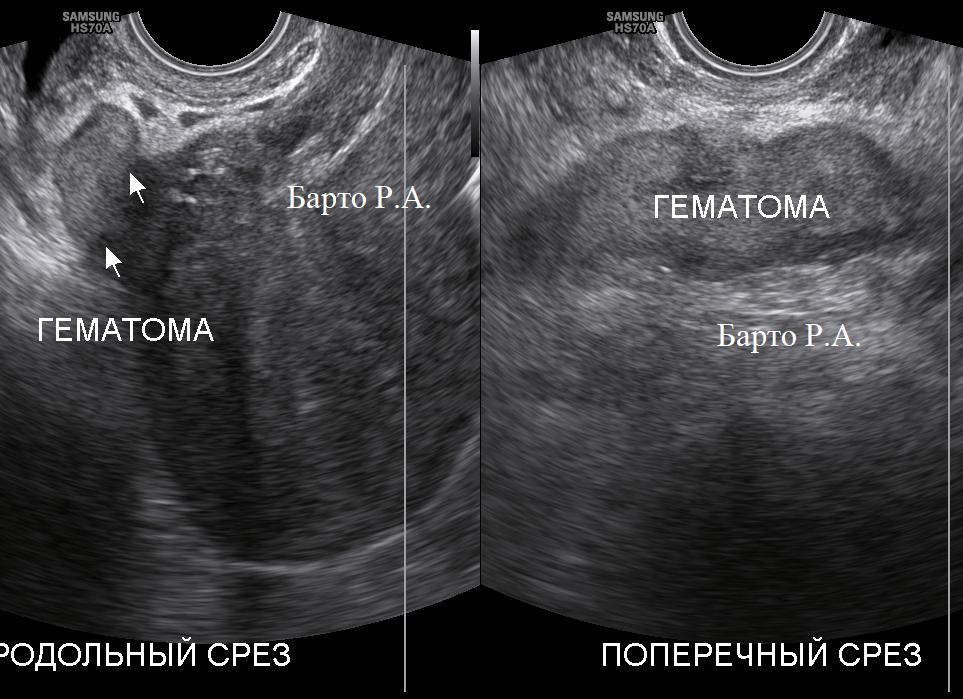

- гематома после кесарева сечения на матке;

Более точным методом определения эндометрита будет проведение гистероскопии. Во время операции возможно оценить состояние эндометрия. Обнаружить сгустки крови в полости матки и произвести их удаление. Детально оценить состояние шва увидеть присутствие гематом на нем.